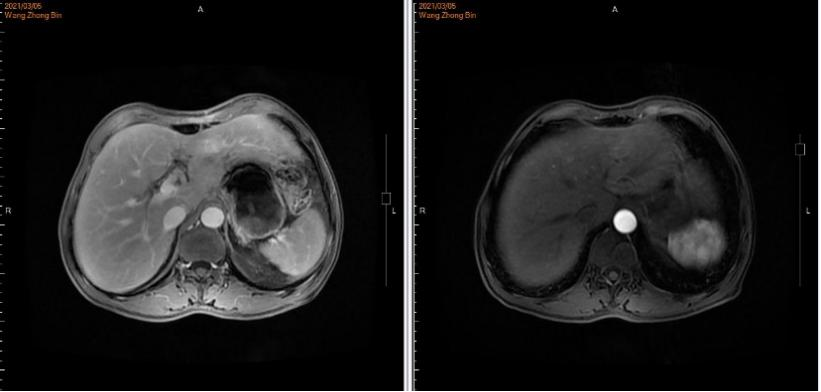

2021年5月12日、7月21日和12月28日:上腹部MRI示:肝、胃术后改变,肝左叶环形强化影,体积较前逐渐减小(最大径分别为15.8mm、14.8mm、10.6mm)。(图5)

图5.上腹部MRI

HER2阳性胃癌是一类独特的疾病亚型,其异质性高的特点要求在治疗时需要采用不同的策略与方法。在该病例中患者确诊为HER2阳性晚期胃癌伴肝转移。ToGA [2]研究证实,曲妥珠单抗联合化疗能显著提高HER2过表达晚期胃癌患者治疗反应率,改善患者生存状况,因此曲妥珠单抗被推荐用于HER2过表达晚期胃癌的一线治疗。该患者姑息性远端胃大部分切除D2廓清B-Ⅱ+Braun消化道重建肝部分切除术后5周行一线曲妥珠单抗联合AS方案化疗时再次发现肝转移病灶。使用赫赛汀®7周期,期间于2021年5月12日、2021年7月21日复查上腹部MRI肝左叶环形强化影,体积较前逐渐减小。

汉曲优®Ⅲ期临床研究[3]结果显示,汉曲优®与原研曲妥珠单抗疗效等效,安全性、免疫原性相似,曲妥珠单抗生物类似药得到NCCN-GI指南、CSCO-GI指南的用药推荐,2020年《中国生物类似药专家共识》也指出:生物类似药与参照药疗效等同、安全性相似,临床上可以替代使用。在本病例中,患者综合经济因素等原因,在使用原研曲妥珠单抗7周期有效后,转换为曲妥珠单抗生物类似药(汉曲优®)继续治疗,目前已使用10周期,并于2021年12月28日复查上腹部MRI示:肝、胃术后改变,肝左叶环形强化影,体积较前逐渐减小,达到PR,显示出良好的疗效和安全性。